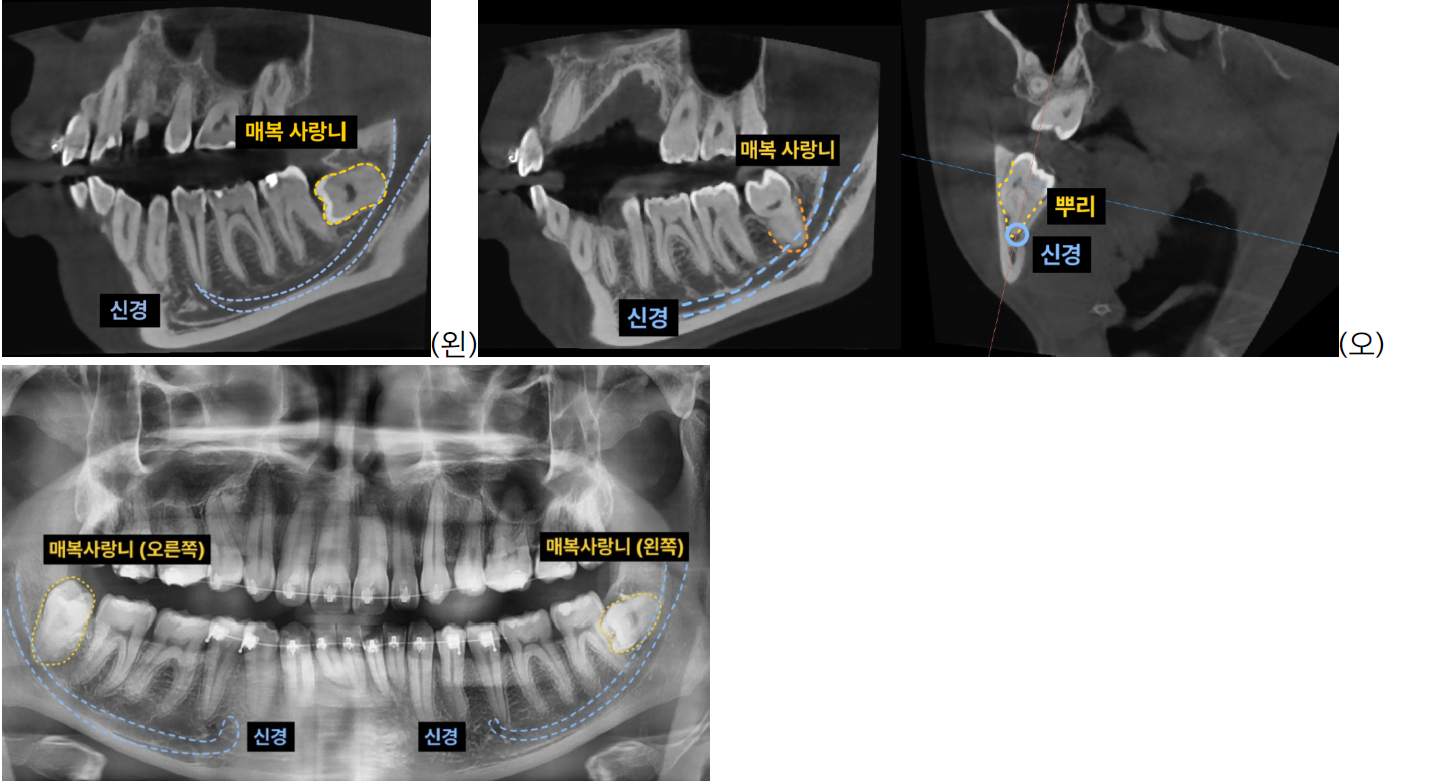

- 3D CT 촬영을 통해 사랑니의 정확한 위치와 매복 정도, 그리고 주변 신경관과의 관계를 면밀히 분석했습니다.

- 왼쪽 아래 사랑니는 가로로 깊이 매복되어 신경과 매우 가까웠으며,

- 오른쪽 아래 사랑니는 신경과 근접한 것은 물론 뿌리가 크고 통통하며 'ㄱ'자 형태로 휘어진 고난이도 형태였습

니다.

2. 정밀 분할 발치: 특히 깊이 매복되어 신경과 가까운 사랑니는 신경 손상 위험을 최소화하기 위해

사랑니의 머리(치관)와 뿌리(치근)를 적절히 분할하여 조심스럽게 발치합니다. 이 과정은 숙련된 의료진의 정교한 기술이 필수적입니다.

3. 성공적인 발치 완료: 좌우 상하 4개의 모든 매복 사랑니를 성공적으로 발치하여, 환자분은 불편함 없이 교정 치료를 위한 충분한 공간을 확보할 수 있었습니다.